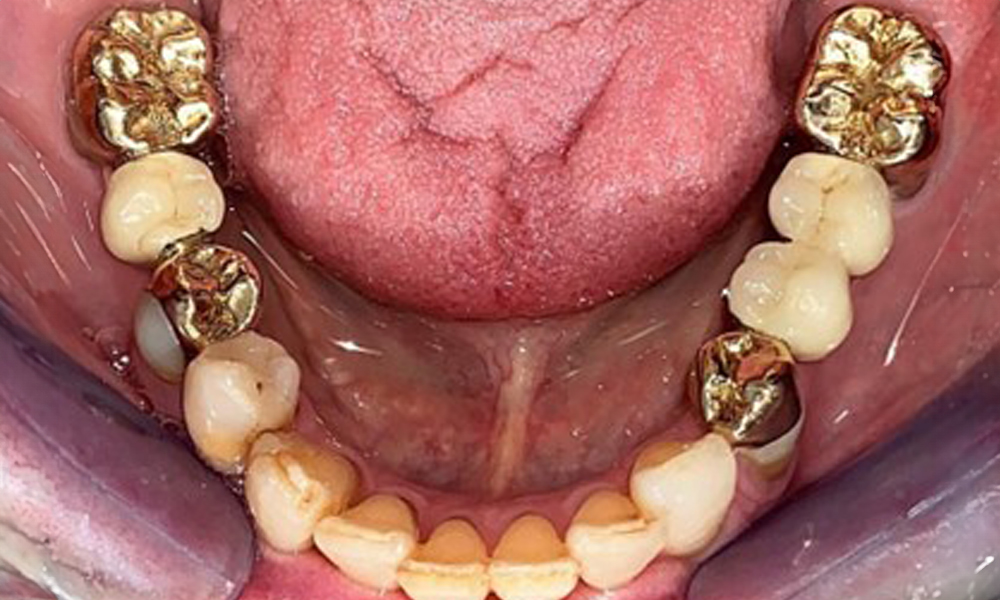

The patient was fitted with a combined removable maxillary telescopic prosthesis more than 25 years ago (Fig. 1, Fig. 2, Fig. 3) and is very happy with her dentures. The patient has an adequate fixed denture for the mandible (Fig. 4).

The dental findings are as follows: Combined removable implant and tooth-supported telescopic prostheses on implants 15, 13, 21, 23, 24, 25 and tooth 11 (Fig. 1, Fig. 2, Fig. 3). The patient was fitted with a fixed mandibular denture. Adequate bridges were present over 37 to 34 and 45 to 47 (Fig. 4), the crown margins were intact and there were no active caries. A composite filling with a marginal gap was present on tooth 43. There was mandibular gingival recession, exposing 1 to 3 mm of root surface. This also applies to 11.

Occlusal view: Maxilla with tooth and implant-supported telescopic prostheses.

Fig. 2: Occlusal view: Maxilla with tooth and implant-supported telescopic prostheses